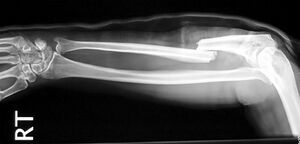

Gebrochener Arm - Speiche - Jane Agnes commons.wikimedia.org, CC BY-SA 3.0

Knochenbrüche werden auch Frakturen genannt. Die entstehen durch direkte (zB Tritt) oder indirekte (zB Sturz) Gewalteinwirkung.

Dadurch kommt es meist zu einer Verschiebung der Bruchenden und dadurch zu einer mehrwöchigen Pause für die betroffene Person.

Mit Hilfe einer Röntgenaufnahme wird der Schweregrad der Verletzung abgeklärt. Es erfolgt entweder eine Behandlung mit Gips oder eine operative Versorgung. In der Rehabilitation unterstützen Mobilisations-, Kräftigungs-, Koordinations- und Ausdauerübungen den Heilungsprozess wesentlich. Die volle sportliche Belastbarkeit ist, je nach Bruchart, erst nach vielen Wochen der völligen Bruchheilung gegeben.